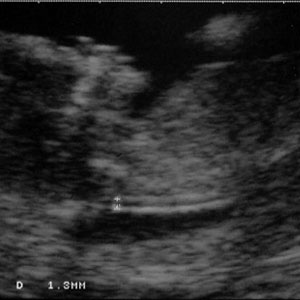

هنگامی که جنین بین 45 تا 84 میلیمتر طول دارد، NT کمتر از 3.5 میلیمتر طبیعی است. NT با رشد جنین افزایش می یابد. تصاویر زیر مقادیر مختلف NT را نشان می دهد.

NT= 1.3 mm :

- جنین با NT =1.3 میلی متر یا کمتر در معرض خطر نیست. اما افزایش NT نیز همیشه به معنی وجود مشکل نیست. در برخی موارد که جنین سندرم داون ندارد نیز مایع پشت گردن آن زیاد است. به همین دلیل پزشک در صورت مشکوک بودن آزمایشات بعدی را برای اطمینان انجام می دهد.